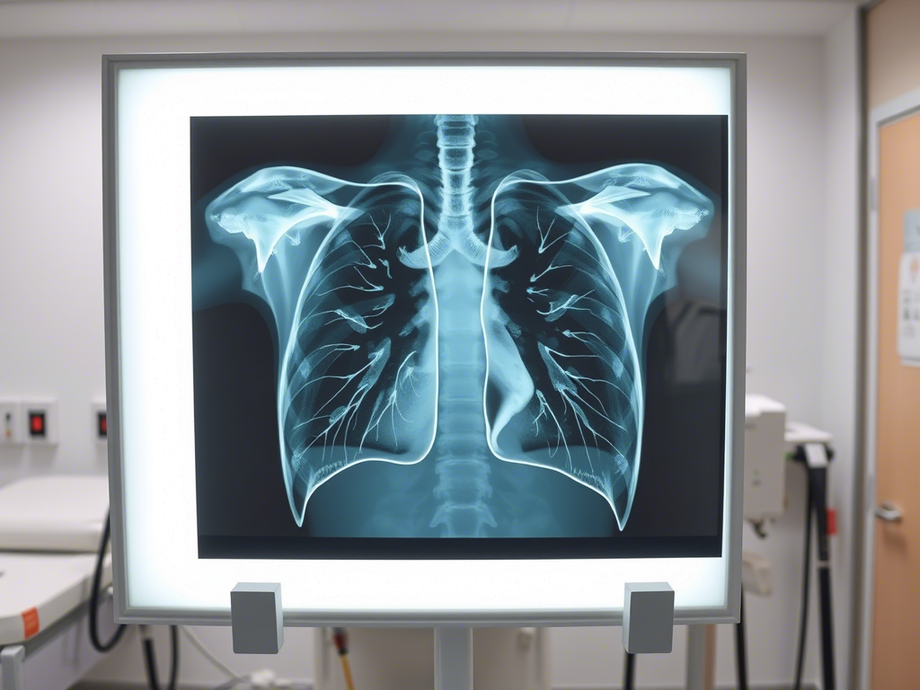

Хроническая обструктивная болезнь лёгких — это часто встречающееся заболевание дыхательной системы. В его основе лежит хронический воспалительный процесс в бронхах, который вызывает изменения в стенках бронхиального дерева. Из-за этого выделяется большое количество мокроты, которая плохо выводится из организма, что приводит к нарушению движения воздуха в бронхах.

Используя методы машинного обучения, FuzzyGuard анализирует звук кашля пациента, слушает, как работают легкие, изучает сканы компьютерной томографии (КТ) легких, после чего объединяет и анализирует всю эту информацию, используя специальные «умные» алгоритмы (нейро-нечеткие сети). На основе этих данных FuzzyGuard делает вывод, есть ли у пациента ХОБЛ, и насколько вероятно, что болезнь разовьется в будущем.